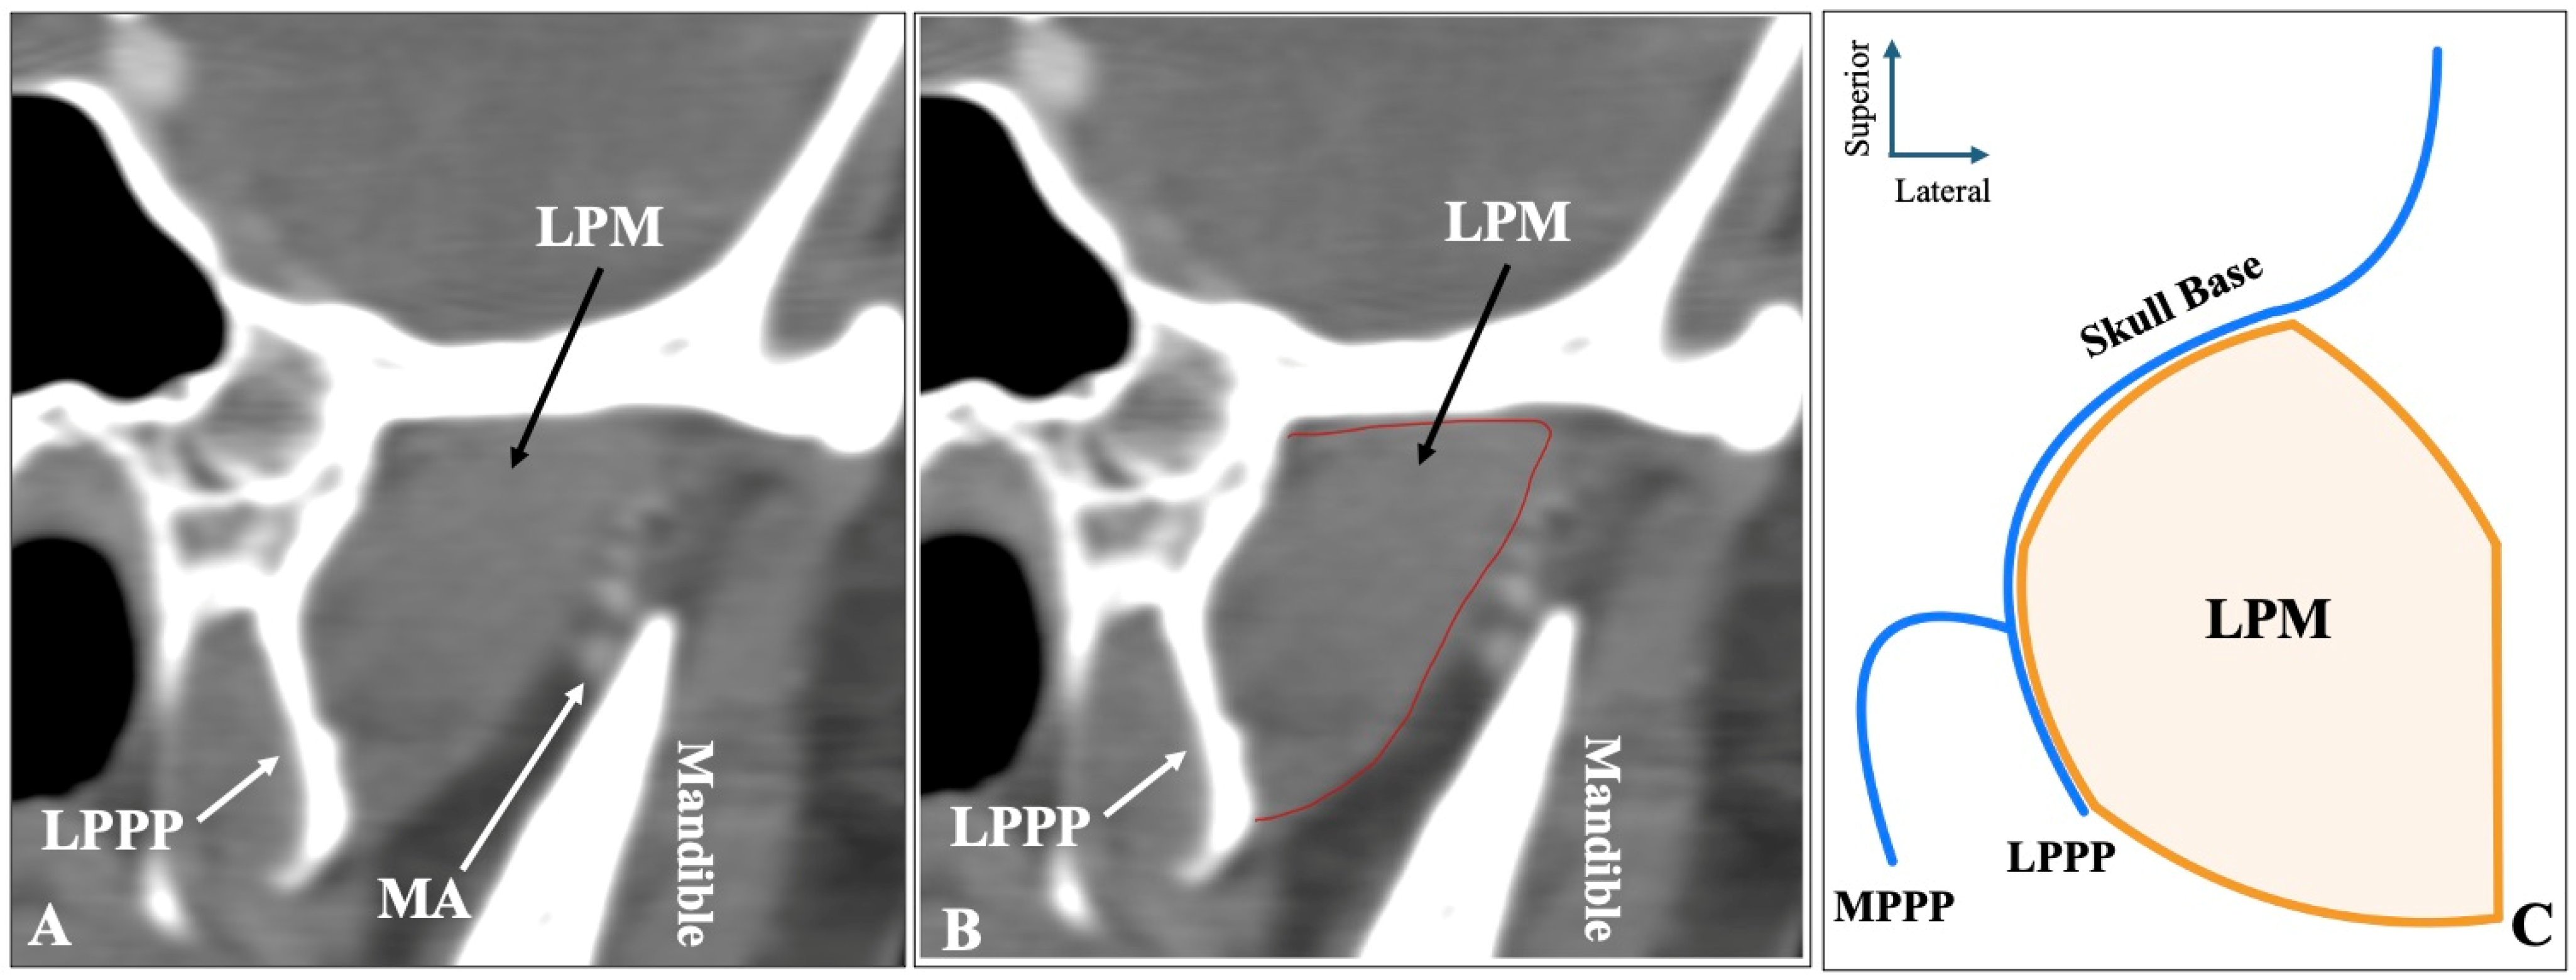

The second most common morphology was the three-headed configuration (superior-middle-inferior) recorded in sagittal slices, observed in 70 sides (14%) (Figure 2). Out of the 70 sides with three-headed LPM, 44 (62.9%) had the MA lateral to the muscle, 16 (22.9%) had the MA medial, and 10 (14.2%) had the artery through the muscle.

Figure 2.

The three-headed configuration of the lateral pterygoid muscle (LPM) is shown in sagittal CTA slices (A,B) and in schematic representation (C). LPMsh = superior head; LPMmh = middle head; LPMih = inferior head; LPPP = lateral pterygoid process plate.